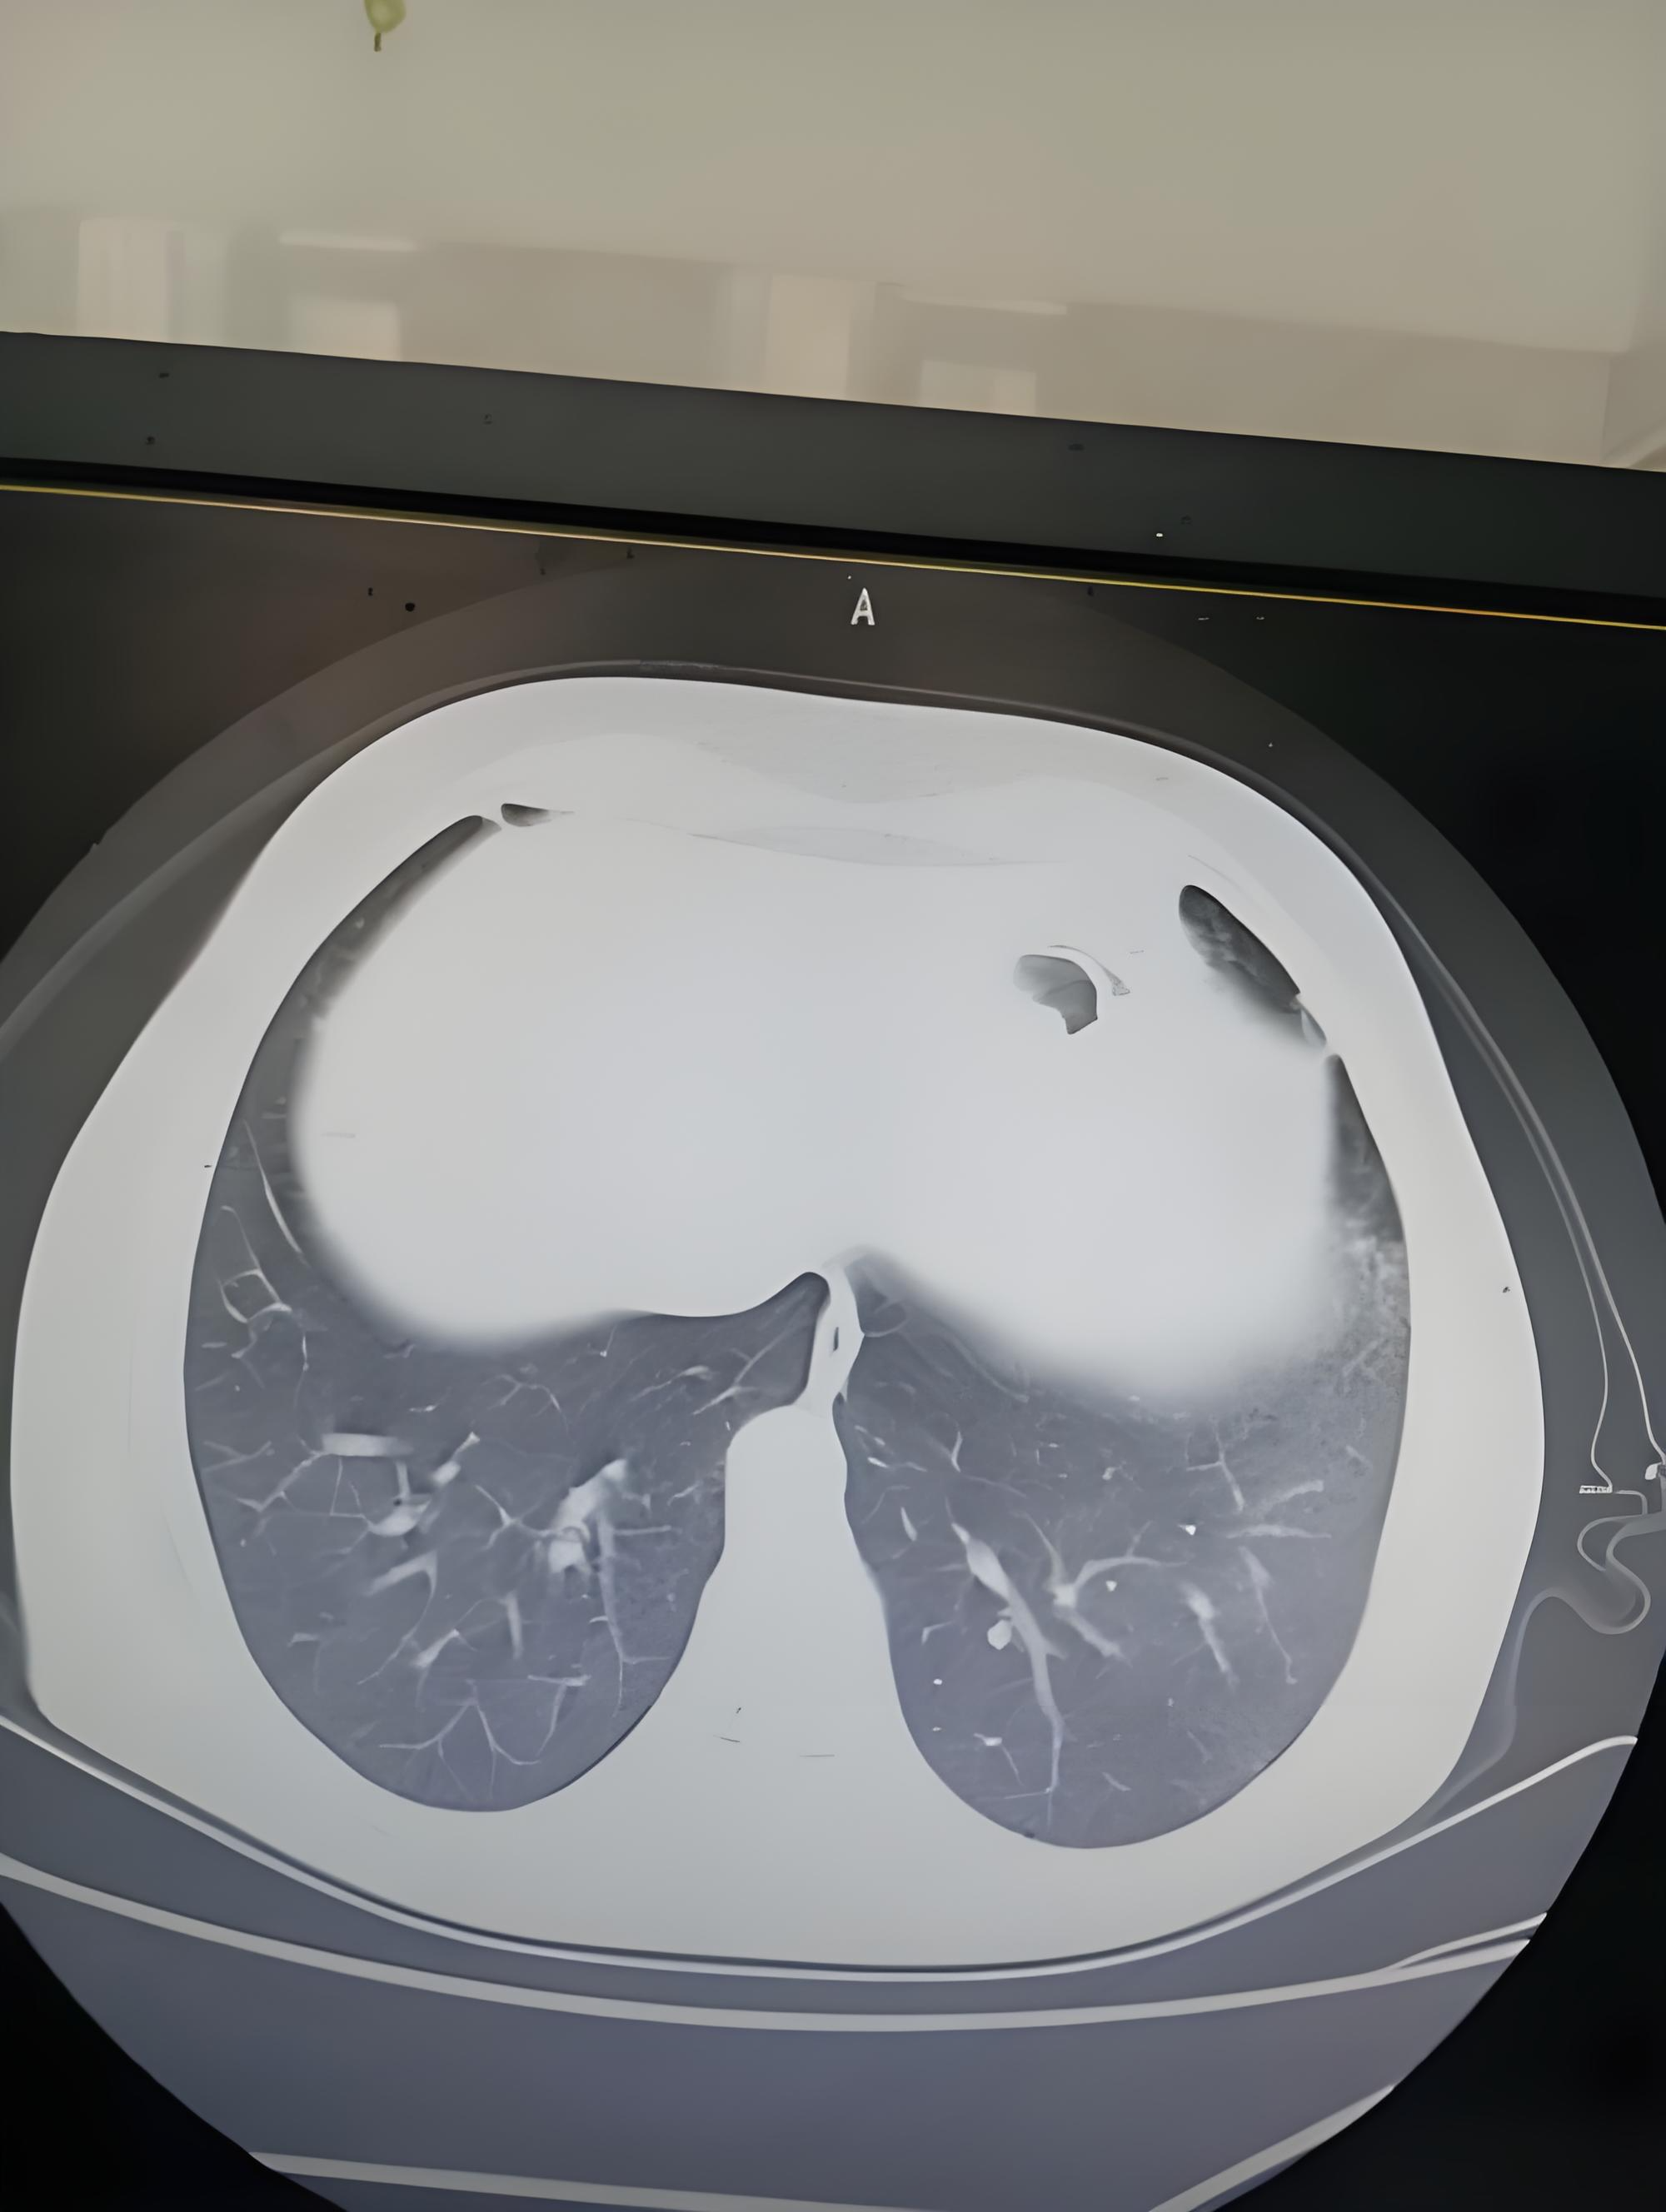

你知道多发肺结节长什么样吗?

气ct表现肺结石图片前纵隔结节膈肌上的肿瘤前纵隔胸腺结节是什么意思

肺结节大小的分类

肺部结节